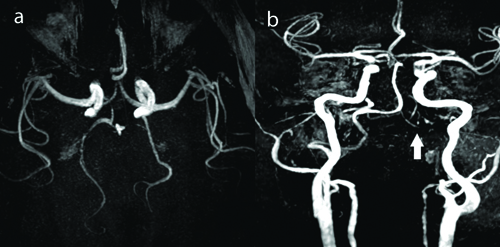

A 45-year-old female patient with no prior comorbidities was admitted with three-day history of high-grade intermittent fever followed by generalised tiredness. There was no history of joint pains, prior headache or seizures. Serology for dengue was positive and she was admitted in the Department of Internal Medicine. She was managed conservatively with hydration and antipyretics. She had drop in platelet counts to less than 10000/μL which required administration of platelet transfusion. Immediately after platelet transfusion, patient developed sudden onset of severe thunderclap headache associated with elevated blood pressures (>160/90 mm). The headache was noted to increase with blood pressure rise. There was no history of weakness of limbs or blurred vision. Clinical examination revealed no focal neurological deficits or meningeal signs. Magnetic Resonance Imaging (MRI) of the brain [Table/Fig-1] showed T2 weighted hyperintensities involving the left occipital and bilateral fronto parietal regions. There was evidence of focal restricted diffusion on Diffusion Weighted Imaging (DWI) sequences and no evidence of contrast enhancement. MR Angio (MRA) [Table/Fig-2] showed evidence of multifocal stenosis and narrowing involving the left vertebral and right posterior cerebral arteries. The scans were discussed with the neuroradiology team and were felt to be suggestive of Posterior Reversible Encephalopathy Syndrome (PRES). The differentials considered were primary CNS angiitis and cerebral venous thrombosis. She was managed with antioedema measures and anti-hypertensive agents-Mannitol at a dose of 0.5 mg/kg/day, hypertonic saline infusion at 15 mL per hour and labetalol 200 mg per day and had complete resolution of symptoms. She was discharged after improvement. At two weeks follow-up, patient was asymptomatic and had no deficits. Repeat MRI done after three months showed complete resolution of the abnormalities seen on the initial scans confirming a diagnosis of PRES [Table/Fig-3].

a) MRA coronal images showing irregularity with multifocal stenosis in right PCA (arrow). b) MRA axial image showing stenosis in Left Vertebral Artery V4 segment (arrow).